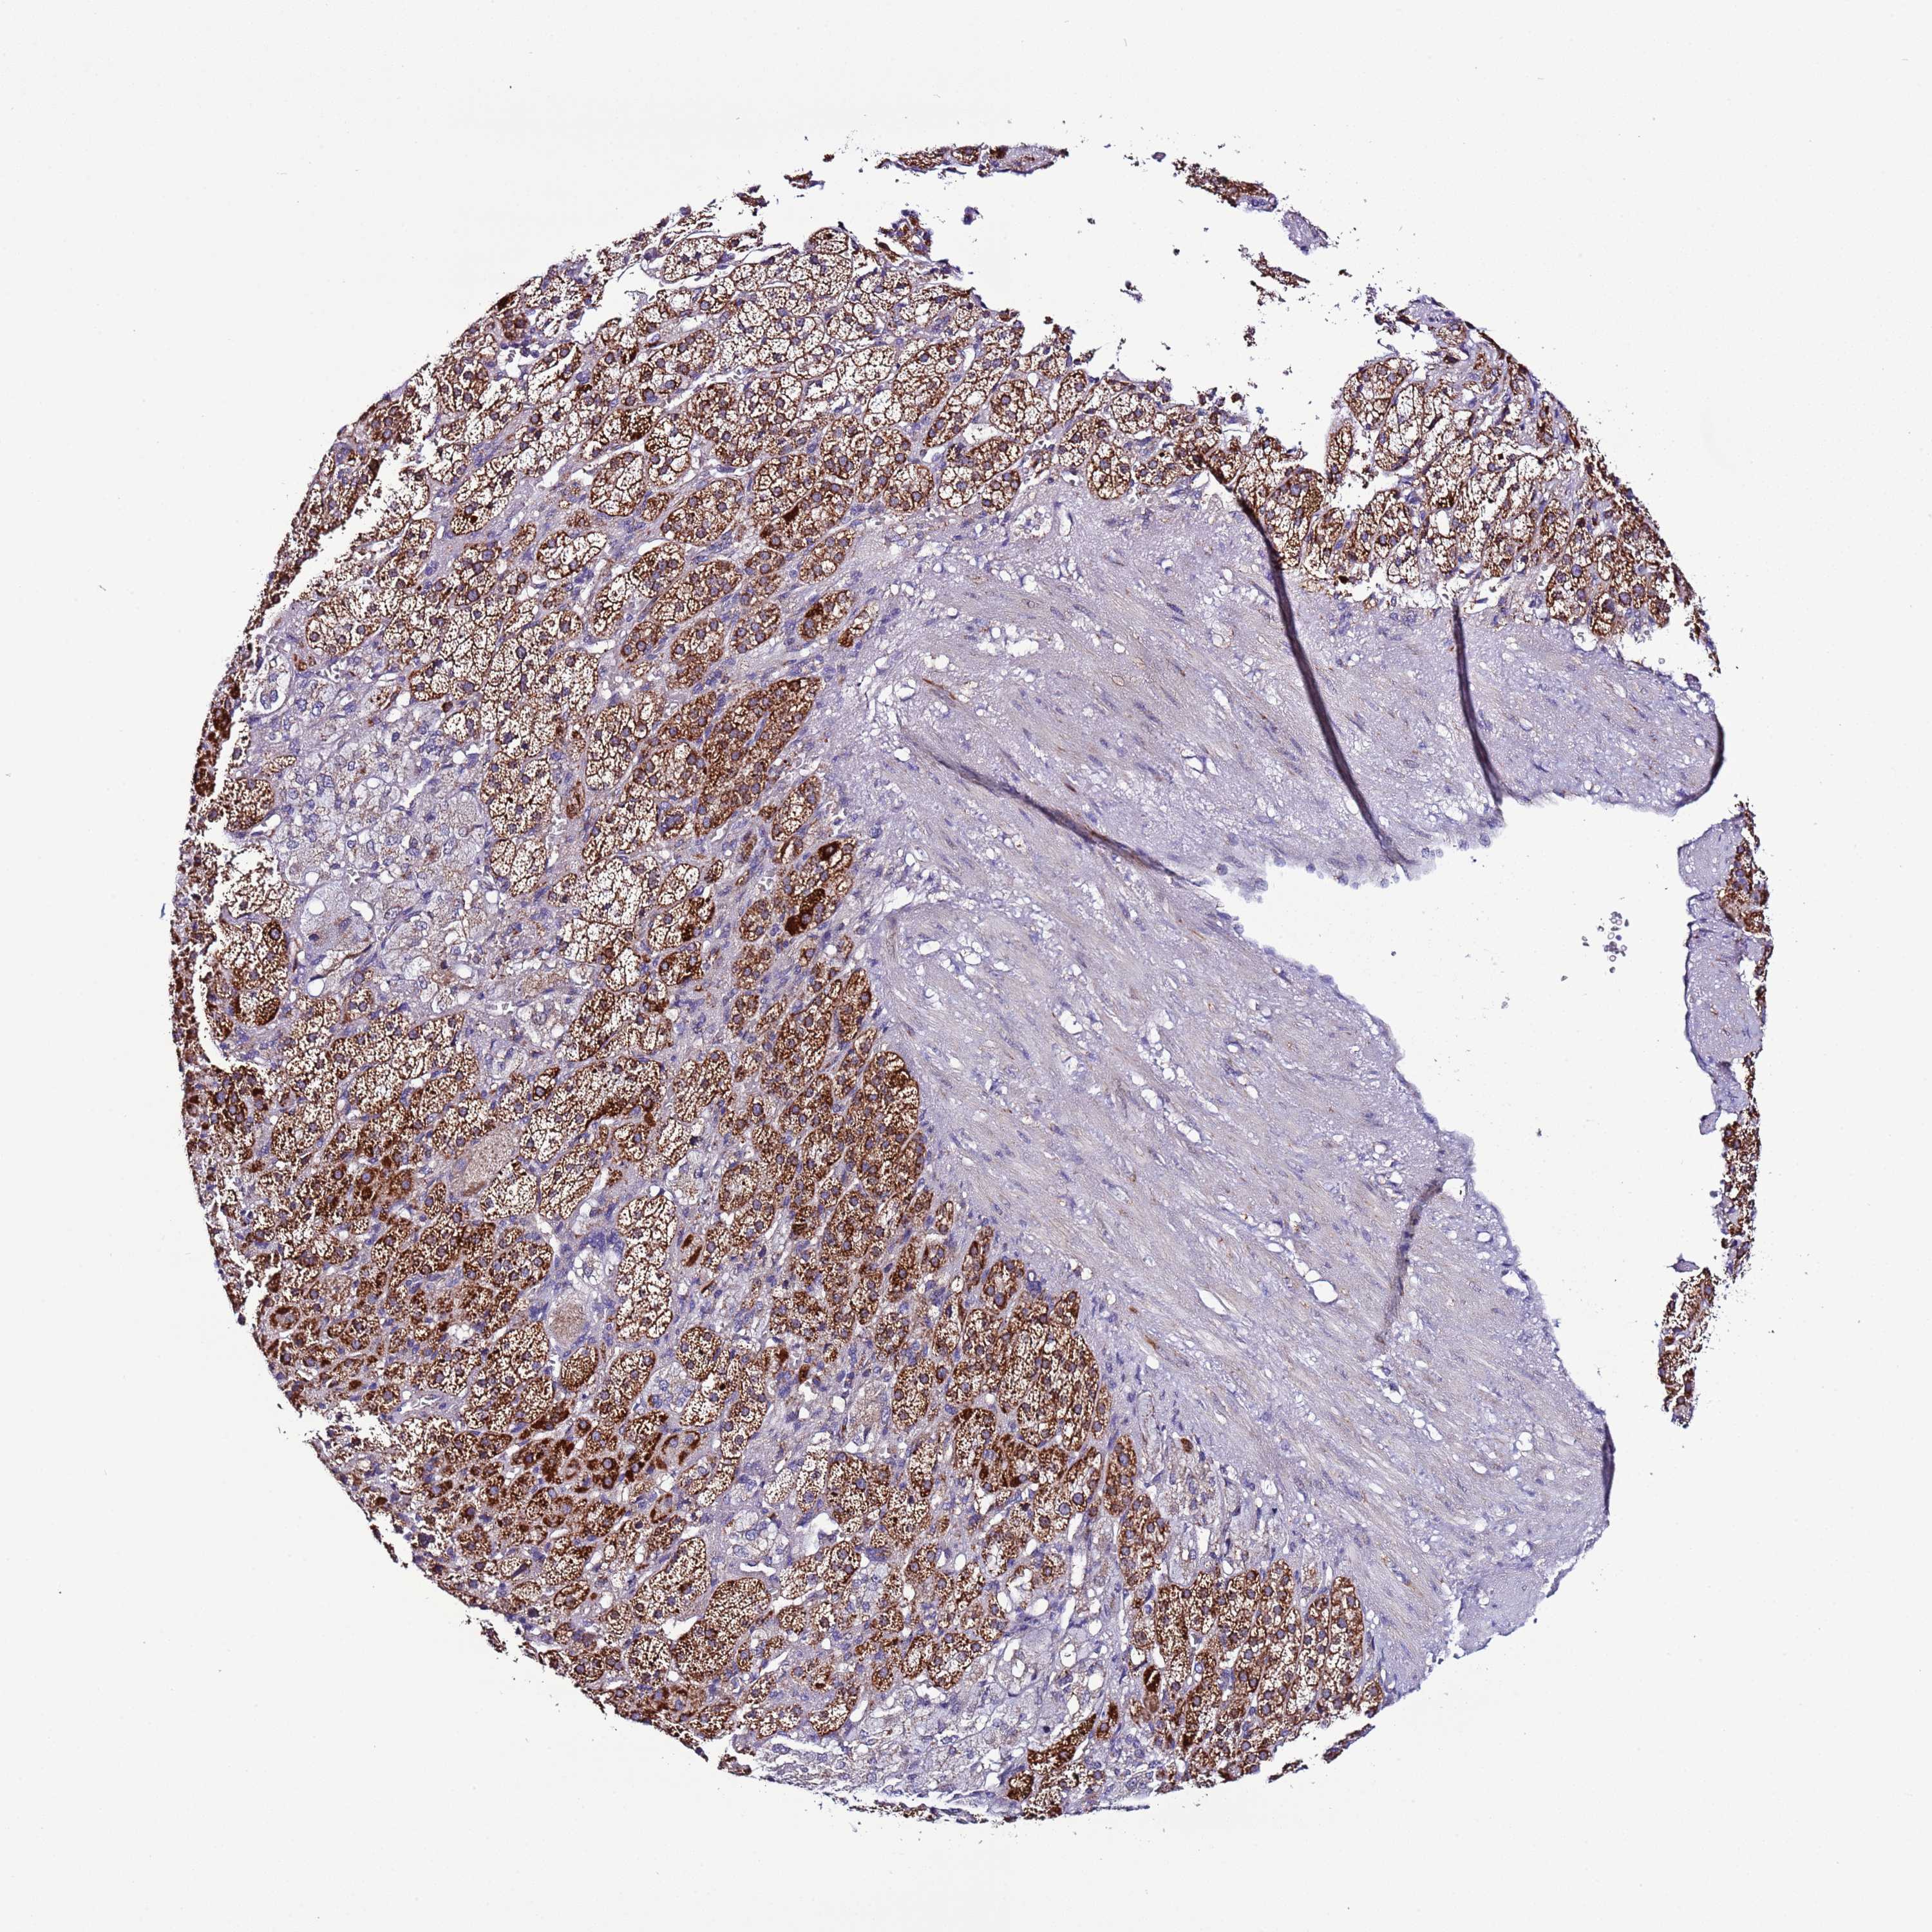

ADRENAL GLAND - Antibody stainingi

Antibody staining in the annotated cell types in the current human tissue is reported as not detected, low, medium, or high, based on conventional immunohistochemistry profiling in selected tissues. This score is based on the combination of the staining intensity and fraction of stained cells.

Each image is clickable and will lead to virtual microscopy that enables deeper exploration of all samples and also displays staining intensity scores, fraction scores and subcellular localization as well as patient and tissue information for each sample.

Antibody HPA047134

Glandular cells High